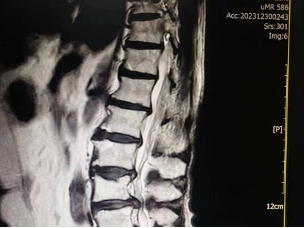

腰椎间盘变性的过程(磁共振示图:正常和退变)

正常的椎间盘:MRI T2加权高信号(图1、2);退变的椎间盘:MRI T2加权低信号(图3、4、5)。

腰椎间盘突出症MRI